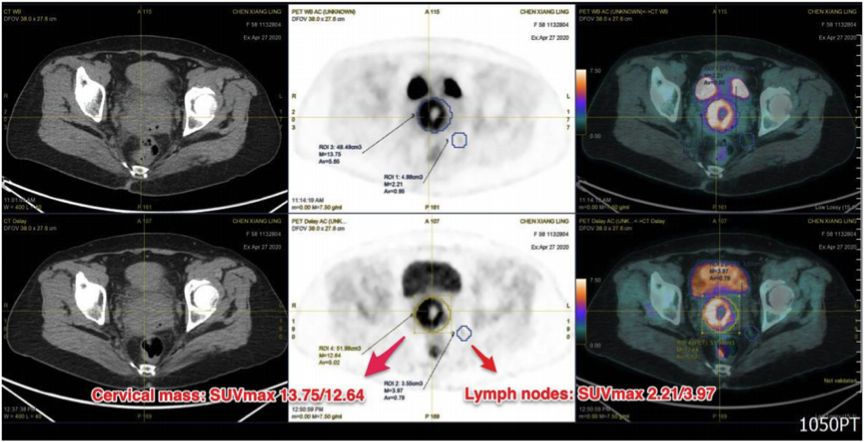

使用F-18-氟脱氧葡萄糖(FDG)进行计算机断层扫描(PET/CT)的正电子发射断层扫描,并显示出一个FDG摄取增强的宫颈肿块。初始和延迟最大标准化摄取值(SUVmax)分别为13.75和12.64。此外,左侧盆腔有两个FDG阳性淋巴结。其中一个测量值为0.94cm,位于左髂内动脉内侧,显示FDG摄取增加,初始/延迟SUVmax为2.21/3.97。另一个为1.8cm,位于左髂外动脉后方,显示中度FDG摄取,初始/延期SUVmaxs分别为6.84/6.23(图2)。它们在MRI成像下与同一病灶相容。根据放射学检查结果,高度怀疑宫颈恶性肿瘤。

图2. PET/CT结合FDG显示宫颈处有一个富含FDG的肿块,左侧盆腔有两个淋巴结受累